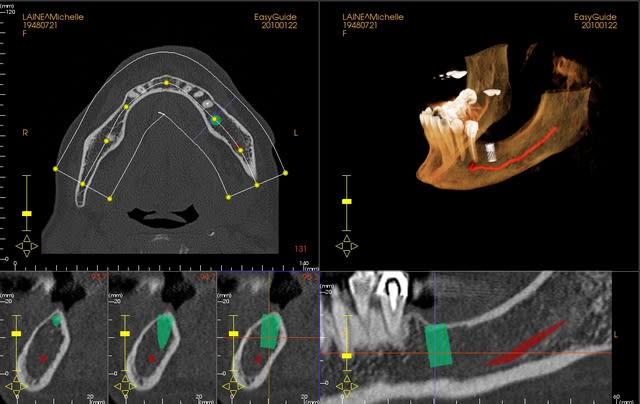

une petite étude de ton cas avec implants osseosped Astra :

12 : 3.5 x 11

13 : 3 x 11 (?)

14 : 3 x 11 (?)

15 : 3.5 x 11 (?)

16 : 4 x 11

17 : 4 x 11

je ne pratique pas donc pas de conseils sur ces implants.

techniquement:

extraction de 12 , curetage soigneux.

vue la qualité osseuse :

si D4 :

saignée à la lame n°15

si D3 :

avec un disque diamanté 10 x 0.3mm incision crestale de 12 à 16 ou 17

puis avec un disque de 20x0.3mm ou à la lame 15 approfondissement de la saignée

puis expansion en "douceur" (sans incision de décharge verticale, à priori car la ligne de crête est relativement droite)

pose de tes implants et dans ce cas, le VitalOs me semble idéal.

la difficulté majeure sera la corticale palatine qui ne semble pas géniale et qui méritera une attention particulière, ostéotome de Tatum +++

honnêtement je ne commencerais pas par un cas comme celui ci sans une solide connaissance de la sensibilité osseuse.

pas de provisoire